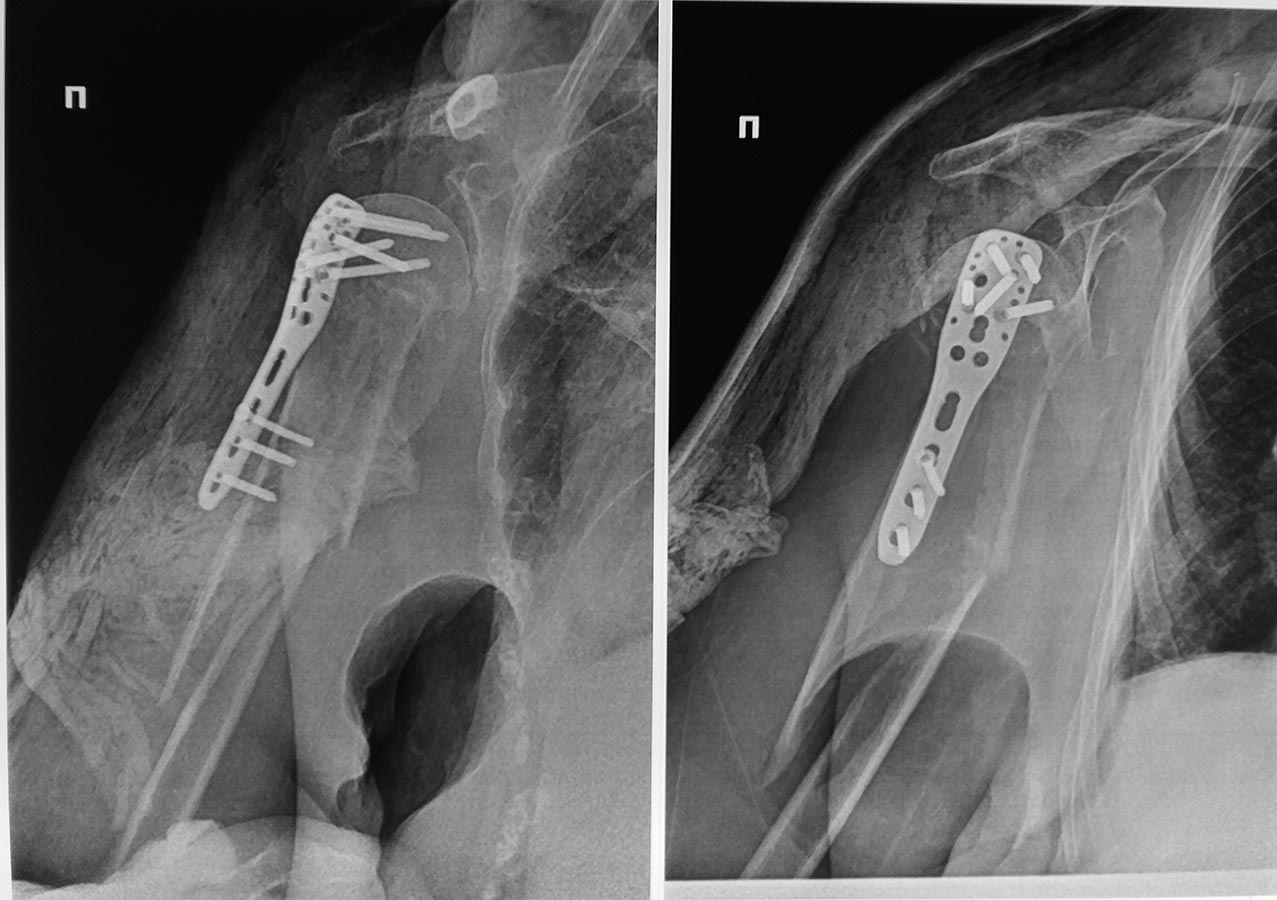

Пациентка Ф. 83 года поступила в клинику с оскольчатым переломом

хирургической шейки плеча. Через 7 дней с момента поступления выполнена

операция МОС. На 6-е сутки после операции падение в палате, результат

периимплантный перелом плеча.Что делать? МОС пластиной. стержнем или

консервативное лечение.